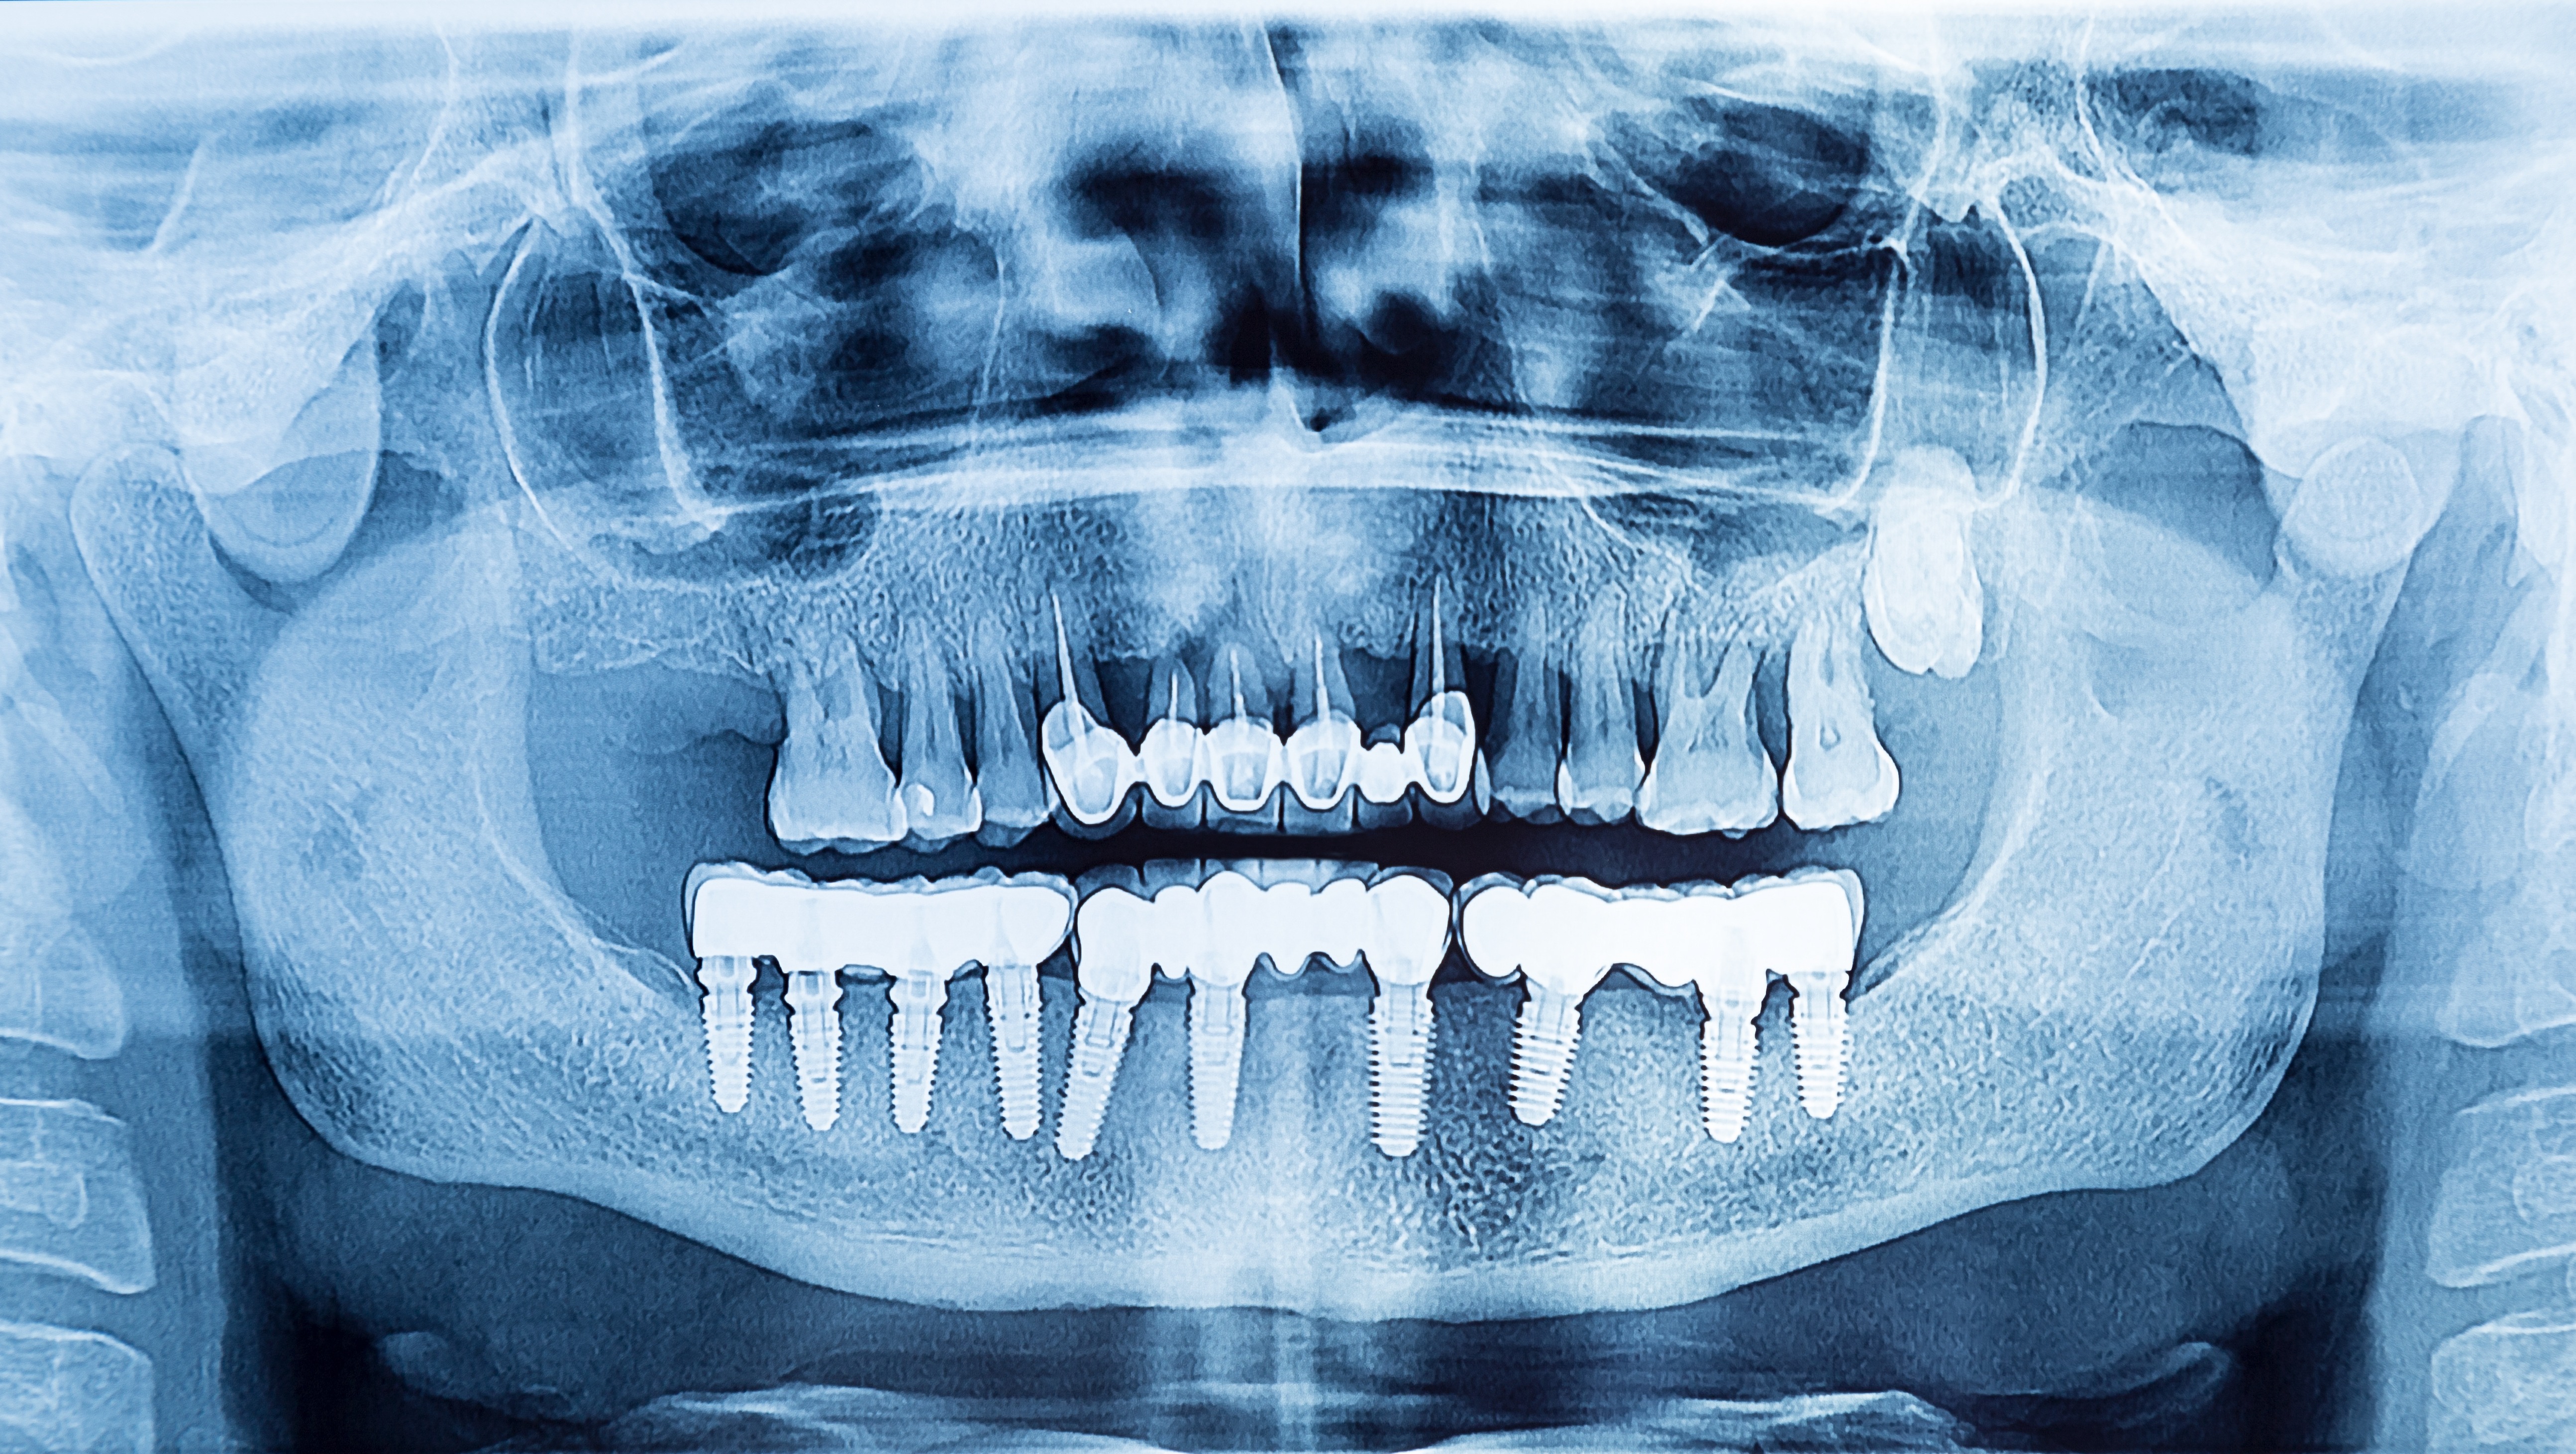

Um peri-implantäre Erkrankungen korrekt diagnostizieren zu können, ist es hilfreich gute und aussagekräftige Röntgenbilder zu haben. Jedoch können gerade peri-apikale Kleinbildröntgen von Implantaten oft „verschwommen“ geraten. Es gibt aber eine sehr einfache Regel, um diese Bilder zu korrigieren und die Implantatwindungen exakt und scharf abzubilden und dadurch das Knochenniveau exakt bestimmen zu können! Diese Regel ist darüber hinaus einfach zu merken und vor allem im klinischen Alltag schnell umzusetzen: